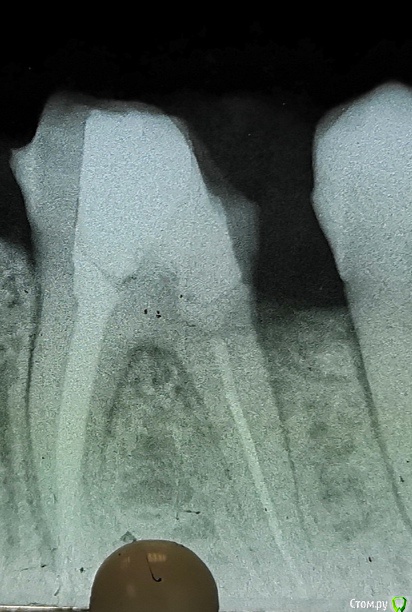

Redaksel Опубликовано 7 июня, 2020 Поделиться Опубликовано 7 июня, 2020 При препарирования зуба 3.6 с дистальной стороны выпала пломба, образовался вот такой дефект.На зуб планируется мк. Вопрос так как культя скошенна в дистальной направлении, то так и оставить или попробовать сделать вкладку или нарастить гомпозитом. Спасибо за внимание Ссылка на комментарий

Марья Моревна Опубликовано 7 июня, 2020 Поделиться Опубликовано 7 июня, 2020 Я за аккуратную вкладку. Заодно и фуркацию визуализируете и проверите. Там могут быть вопросы. Ссылка на комментарий

Stomart Опубликовано 7 июня, 2020 Поделиться Опубликовано 7 июня, 2020 Если после препарирования остальные три стенки остались, то я бы обошелся гомбозитом. Ссылка на комментарий

Redaksel Опубликовано 7 июня, 2020 Автор Поделиться Опубликовано 7 июня, 2020 Да 3 стенки есть, меня одно смущает композит на композит, может даже сделать канавки в нем для "ретенции", как думаете? Ссылка на комментарий